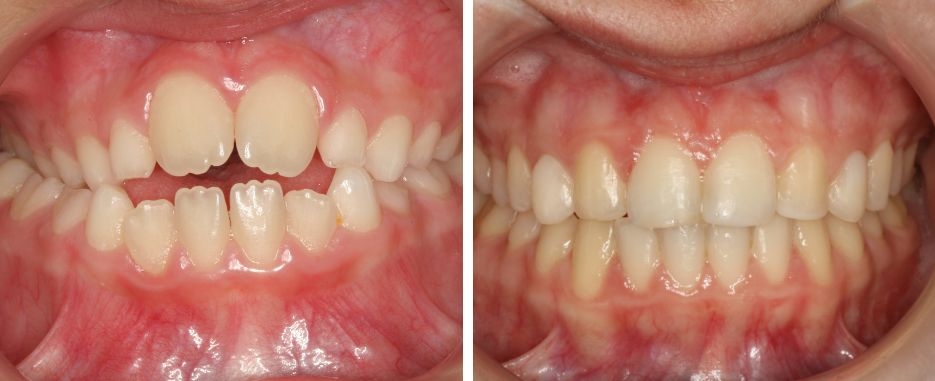

La mordida en tijera se origina cuando los dientes y la mandíbula no se desarrollan de una forma adecuada. Es una situación que implica a ambas arcadas, ya que en el plano transversal, estas no encajan de una manera correcta. Por norma general, es el maxilar el que sobresale y termina cubriendo casi por completo la mandíbula. Es decir, que al no haber contacto entre una y otra arcada, la mordida del paciente no es 100 % eficiente durante el proceso de la masticación.

Es una de las maloclusiones que más problemas funcionales y estéticos causa al paciente, por lo que hay que abordarla cuanto antes. Lo más aconsejable es atenderla en la infancia, si bien puede tratarse de forma eficaz también durante la edad adulta.

Aunque pueda parecer una situación difícil de resolver, existen alternativas que reportan muy buenos resultados. Para poder corregir la mordida en tijera hay dos soluciones principales: el uso de una ortodoncia o la cirugía ortognática.

La ortodoncia es el método más empleado para abordar esta problemática. Lo ideal sería utilizarla en edades tempranas, esto dependerá de la fase de crecimiento del paciente. En ese momento vital hay más posibilidades de guiar correctamente el crecimiento de los dientes. También es más fácil moldear los huesos dentales, su tamaño y posición. El ortodoncista, haciendo uso de la ortodoncia interceptiva, puede mover la estructura ósea para que esta tenga un desarrollo adecuado.